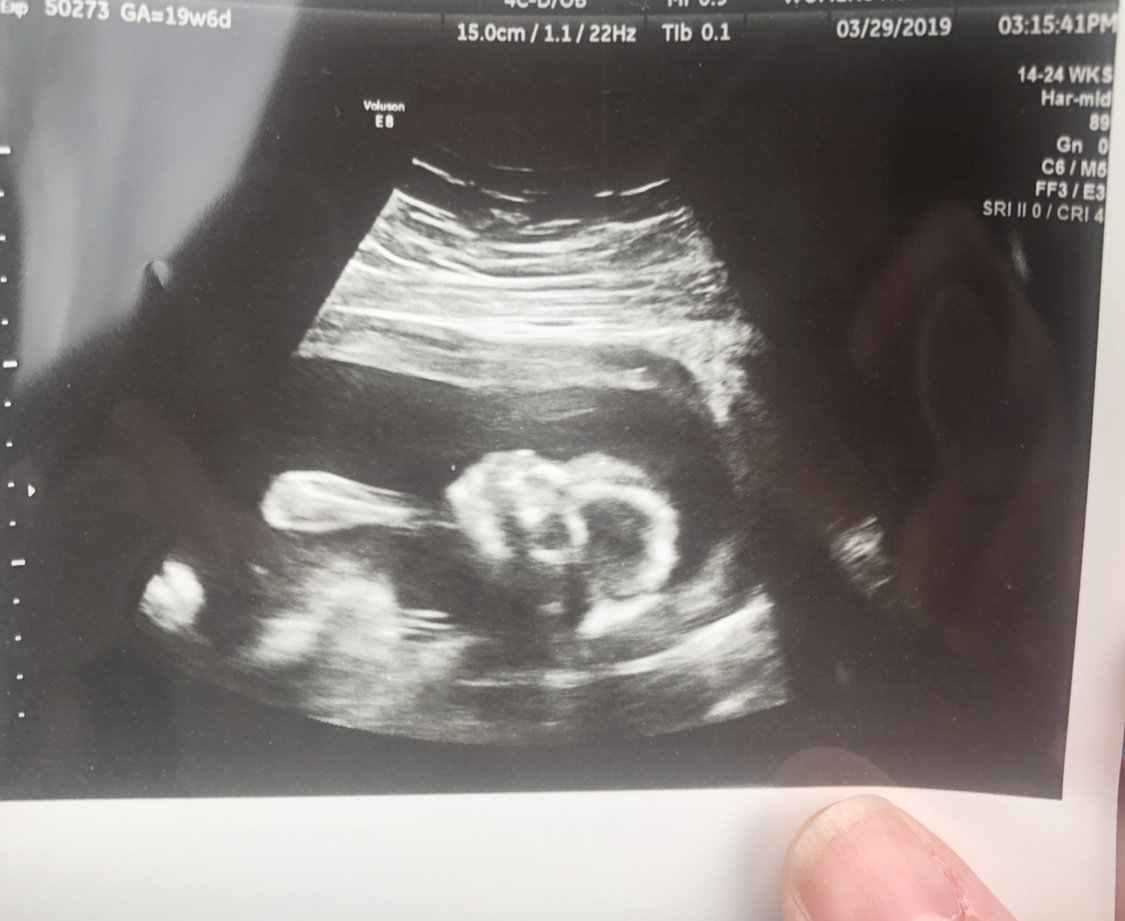

Guys. Guys. Omg. I can post one now!!!! Little girl at 19+4. Im over the moon with getting to see her for the first time! And you know, to find out she’s a girl!!!